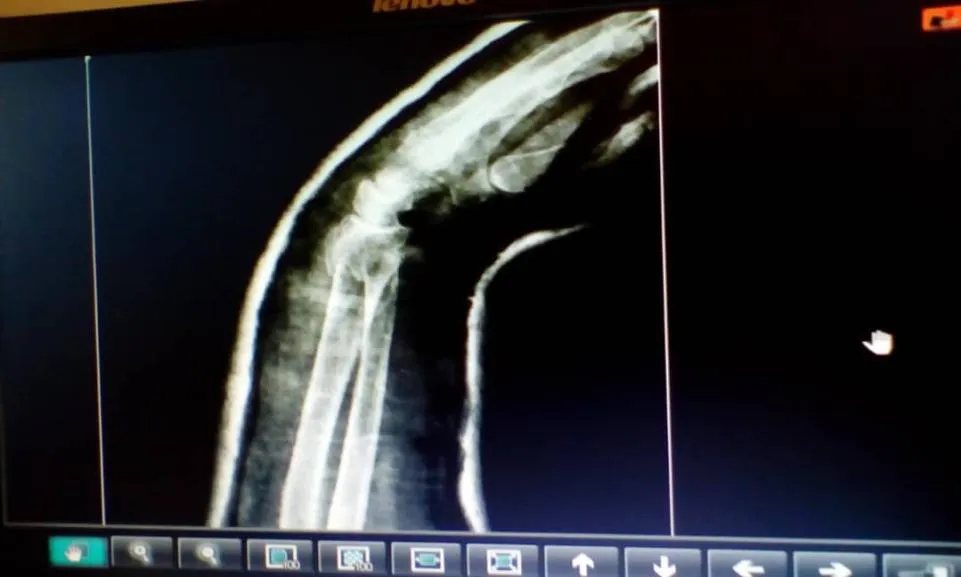

Para el día lunes se realizaron las imágenes de Rx de control para ver la evolución de la paciente